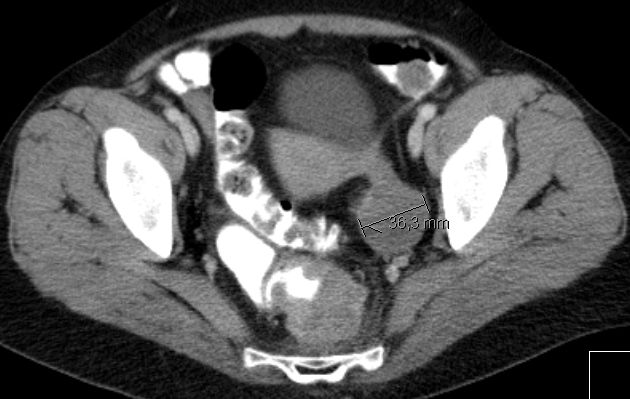

MRT sT2W TSE![]() | |||

MRT sT2W TSE![]() | ||||